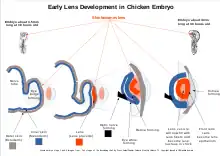

Embryology

The lens vesicle is developed from surface ectoderm.[16] It will separate from surface ectoderm at approximately day 33 in a human and only 3 days for a chicken. Lens capsule developed from basal lamina of lens vesicle will cover early lens fibers. Capsule is evident at 5 weeks of human gestation and begins its role in protecting and supporting the lens interior.[10]